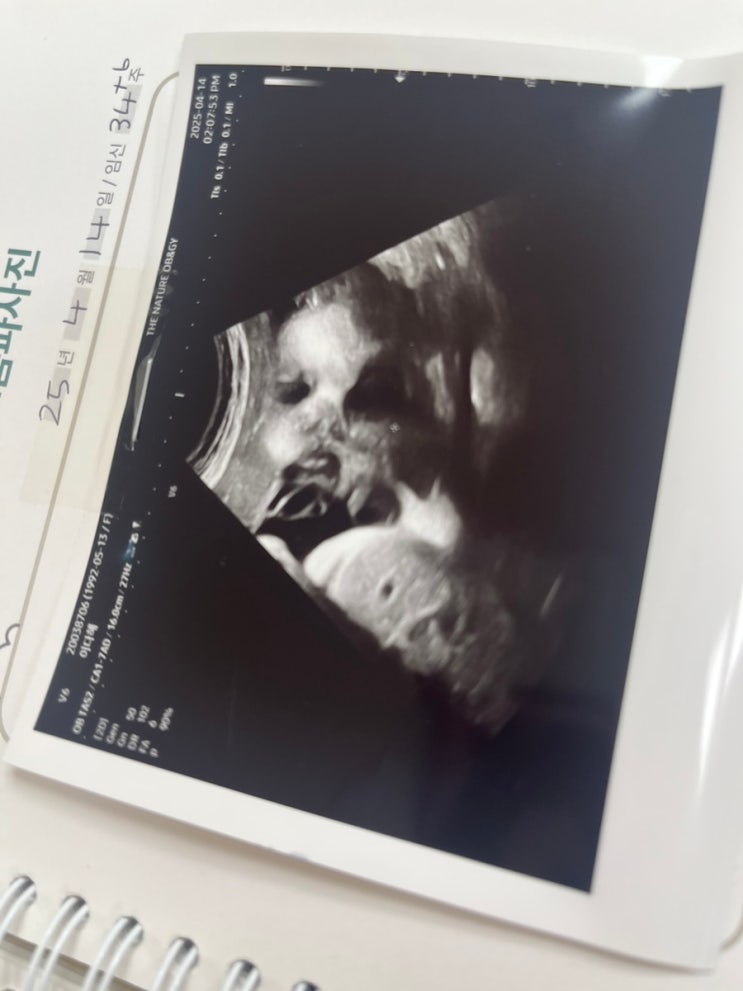

나 자는데 갑자기 딸 자랑하러 방에 들어옴 어이없음 ㅋㅋㅋㅋㅋㅋ 아빠가 진짜 고생 많았던 5월 앞으로 더...